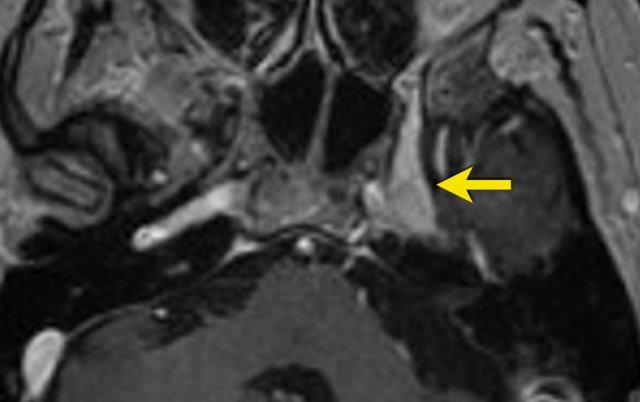

Bệnh nhân nam 70 tuổi có tiền sử u hắc tố (melanoma) và đã được khoét bỏ hốc mắt. Gần đây, bệnh nhân xuất hiện cảm giác ngứa ran và tê bì ở nửa mặt trái. Các triệu chứng này không thể gây ra theo ý muốn và đáp ứng tốt với thuốc giảm đau.

Hãy duyệt qua các ảnh chuỗi xung T1W 3D sau tiêm thuốc tương phản từ theo mặt phẳng axial và coronal, sau đó tiếp tục đọc.

Hình ảnh chuỗi xung T1W 3D sau tiêm thuốc tương phản từ theo mặt phẳng axial và coronal cho thấy hình ảnh dày và ngấm thuốc của nhánh V1 tại khe ổ mắt trên (a và b, mũi tên), nhánh V2 tại lỗ tròn (a và b, mũi tên đứt nét), và nhánh V3 tại lỗ bầu dục (c và d, mũi tên).

Các bất thường này gợi ý hình ảnh lan rộng quanh thần kinh của u hắc tố.